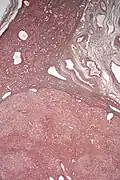

| Micrograph of a hepatic adenoma (bottom of image). H&E stain | |

Pathologic diagnosis

Hepatic adenomas are, typically, well-circumscribed nodules that consist of sheets of hepatocytes with a bubbly vacuolated cytoplasm. The hepatocytes are on a regular reticulin scaffold and less or equal to three cell thick.

The histologic diagnosis of hepatic adenomas can be aided by reticulin staining. In hepatic adenomas, the reticulin scaffold is preserved and hepatocytes do not form layers of four or more hepatocytes, as is seen in hepatocellular carcinoma.

Cells resemble normal hepatocytes and are traversed by blood vessels but lack portal tracts or central veins.